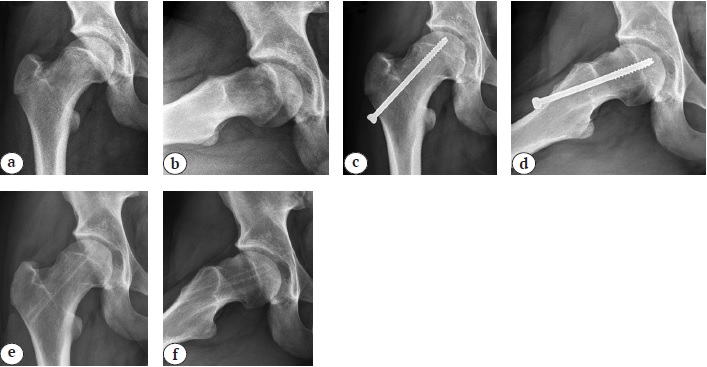

Форма проксимального эпиметафиза бедренной кости на контралатеральной стороне оказалась нормальной во всех 32 наблюдениях. В качестве примера отсутствия ремоделирования проксимального эпиметафиза бедренной кости в послеоперационном периоде могут служить рентгенограммы пациента из IV группы (рис. 6). На предоперационных рентгенограммах визуализируются смещение эпифиза кзади на 17° и книзу на 8°, положительный симптом «сегмента» и костный выступ на передней поверхности шейки бедренной кости. На рентгенограммах, выполненных на 19-м году жизни, определяется типичная деформация cam-типа, сохраняются положительный симптом «сегмента» и костный выступ на передней поверхности шейки бедренной кости исходной выраженности.

Рис. 6. Рентгенограммы правого тазобедренного сустава в переднезадней проекции и в проекции Лауэнштейна пациента 14 лет 9 мес.: a, b — непосредственно перед операцией; c, d — через 2,5 года после операции перед удалением металлоконструкций; e, f — через 3,5 года после операции при заключительном обследовании на 19-м году жизни